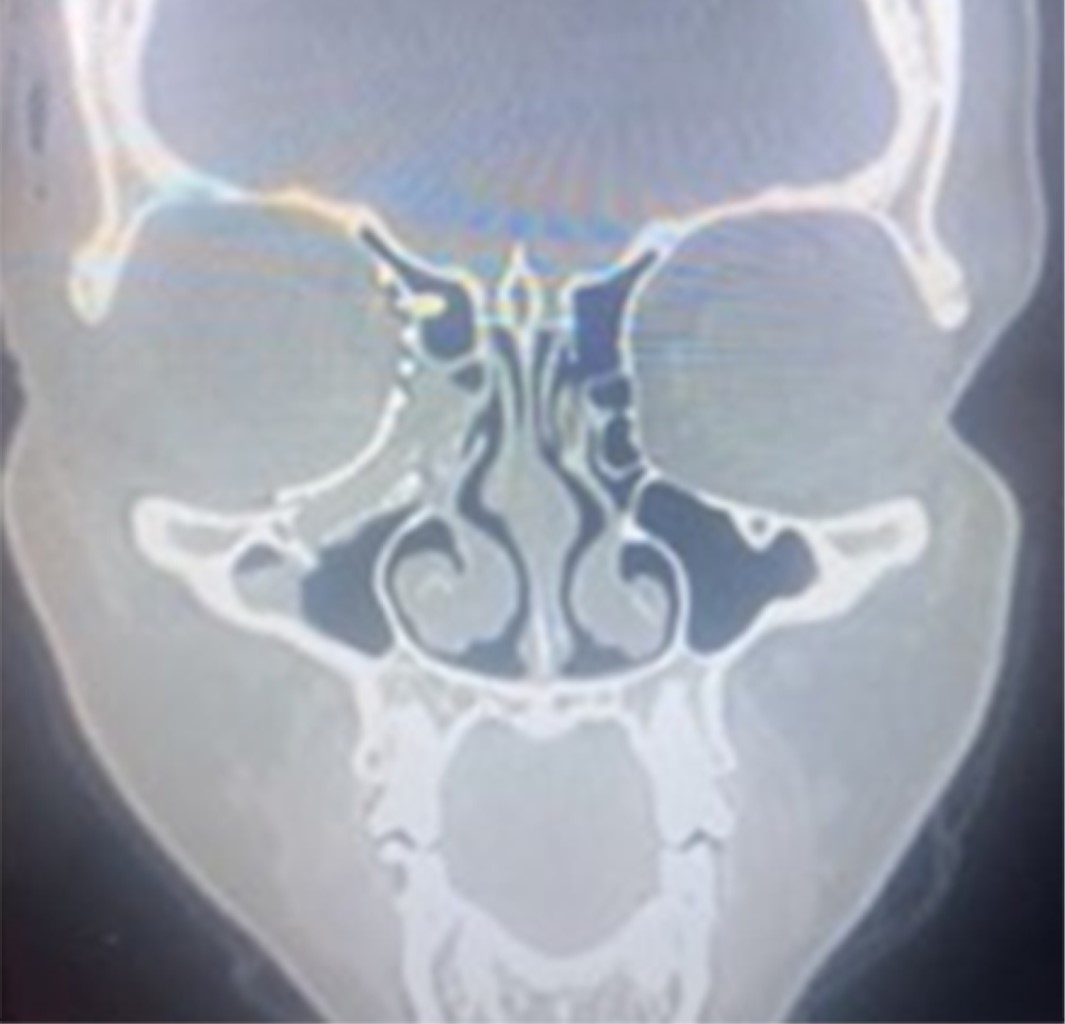

CASO TRES

Paciente masculino, 30 años, víctima de accidente de motocicleta, sin protección, con colisión frontal con otra motocicleta, recibió atención del equipo de Cirugía Oral y Maxilofacial y Traumatología del Hospital da Posse en la ciudad de Nova Iguaçu, Río de Janeiro. Presentaba un traumatismo en la región orbitaria derecha, que evolucionaba con signos clínicos de enoftalmos, distopía y oftalmoplejía en mesial y supraversión.

La tomografía de la cara muestra afectación de la pared orbital medial que a su vez afecta al suelo orbital y a la región de la zona clave (Figura 9).

Se realiza abordaje bicoronal y subtarsal para la resolución del atrapamiento de tejidos blandos, de la musculatura del recto inferior y medial así como la reducción de la fractura. Se utiliza para la reconstrucción una malla orbital para el correcto reposicionamiento y reconstrucción de la zona clave, así como del contenido orbital. La tomografía computarizada del postoperatorio inmediato mostró la reconstrucción de la órbita mediante malla y sistema de fijación con tornillos de 1.5 mm; se observa el correcto contorno de la órbita, el retorno de su contenido y forma así como la importancia de la adaptación posteromedial y la correcta reducción y reconstrucción de la zona clave para el éxito y resolución del caso (Figuras 10, 11 y 12). Seguimiento de 60 días postoperatorios sin presentar restricciones de movimiento ocular, distopía y diplopía, retorno de la agudeza visual y edema leve en región periorbitaria.